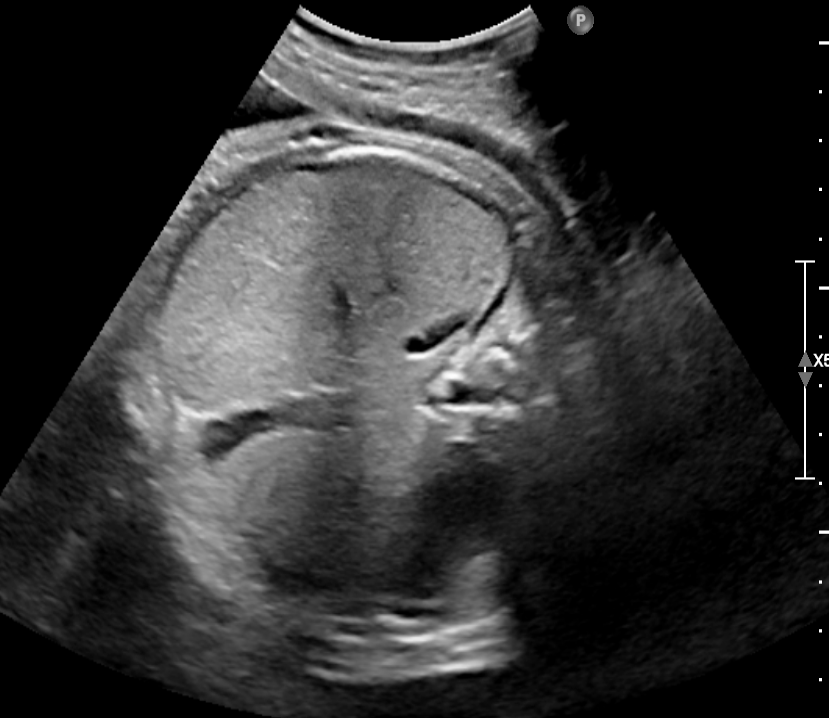

TABLE I: Sample outputs comparing reference captions with captions generated by the proposed model.

Uterine Ultrasound Image Reference Caption Generated Caption

Consequently, the CNN-BiGRU model outperformed the other baseline models regarding BLEU and ROUGE scores and demonstrated lower loss values, underscoring its effectiveness in this application. Moreover, Table I provides further evidence by illustrating sample outputs that compare reference captions with captions generated by the CNN-BiGRU model. This comparison vividly showcases the model’s ability to generate high-quality captions through its robust bidirectional processing capabilities.